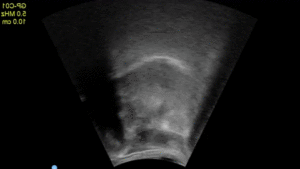

We use ultrasonic imaging tools to investigate the dorsal surface of the tongue and the surface of the lateral pharyngeal walls for stop consonant productions in both typical and atypical speakers including talkers with Parkinson’s disease, L2 speakers of English (FSU CRC Seed Grant, 2025-2026 ISL Planning Grant)